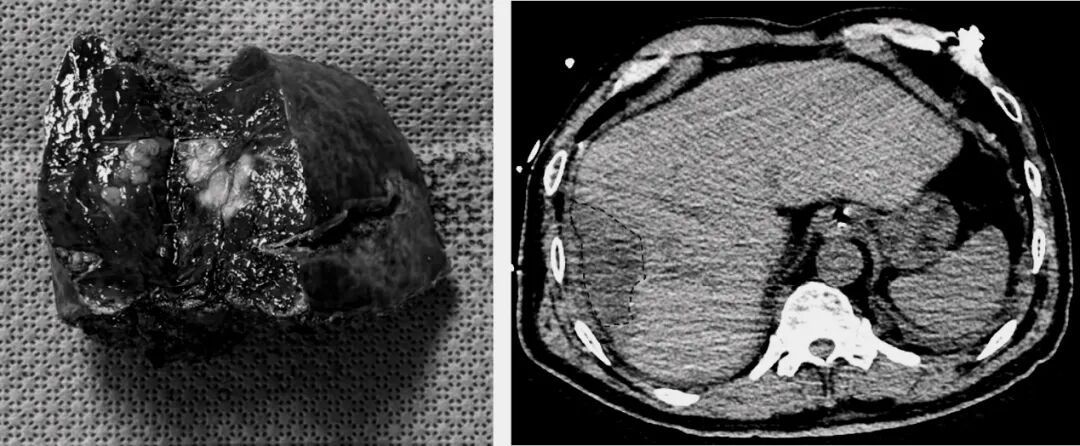

经过周密的准备,手术如期进行。术中运用了肝胆外科的特色技术——腹腔镜超声对肿瘤进行精准定位识别,并结合术中荧光染色实现肝段边界的清晰显影,从而辅助规划精准切除范围。在高清腹腔镜的放大视野下,蒋小峰教授操纵着精细的器械,在方寸之地稳健操作。借助这些先进技术的引导,他巧妙避开重要血管和胆管,如同进行一场精密的“肝脏雕刻”,最终完整切除肿瘤,并最大限度保留健康肝组织。手术过程出血极少,患者生命体征始终保持平稳。

精准、完整切除肿瘤

术后第4天复查

得益于精准微创的手术和贯穿始终的加速康复外科(ERAS)理念,陈伯的恢复超出了所有人的预期。术后次日,他即可在搀扶下下床活动。“真系冇谂到,第二日就可以落床行,伤口又细。这里的医生技术高超,护士们耐心细致,让我这个老人家少受了很多罪。从香港过来,这个决定做对了!”陈伯的脸上露出了久违的笑容。在医护团队的精心照护下,他顺利度过了康复期,复查显示肿瘤切除彻底,肝功能良好。